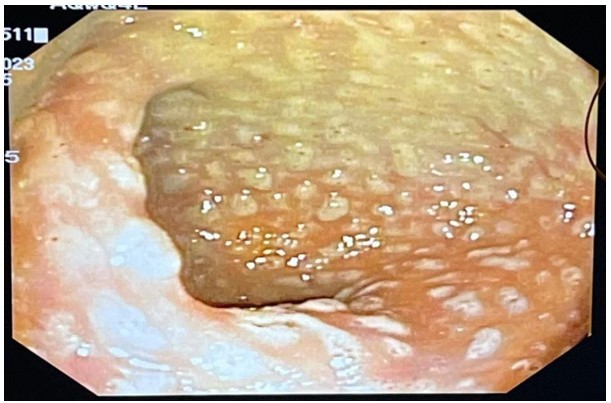

- A colonoscopy was performed, revealing diffuse yellowish, whitish plaques with fibrinous exudate. These endoscopic findings were consistent with the classic pseudomembranous colitis associated with C. difficile infection.